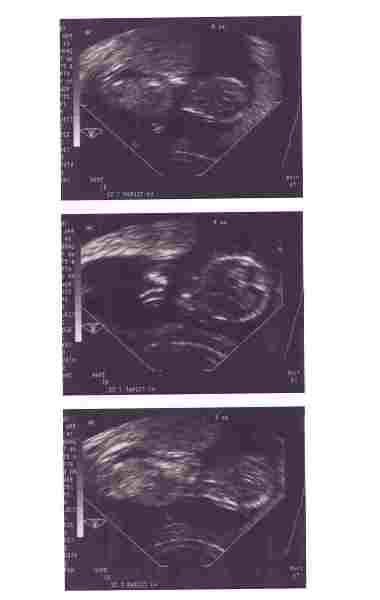

Megpróbálom feltölteni a 12 hetesen készült első fotót a babánkról. Remélem, azért kivehető lesz, bár eléggé le kellett kicsinyítenem a felbontását a feltöltéshez.

A két szélső képen az egész baba látszik (egyébként 71 mm), és a középsőn pedig felülnézetből a feje, és a kezének kicsit ujjacskái (amik kicsit egybemosódtak a fotón, de a gépen tisztán látszott 5 kis pötty).

12 hetesen

12 hetesen

12 hetesen